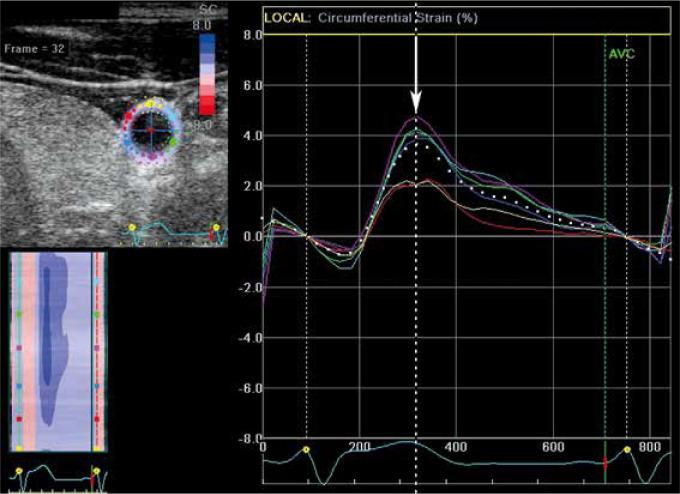

Peripheral arterial response during haemodialysis - is two-dimensional speckle-tracking a useful arterial reactivity assessment tool?血液透析期间的外周动脉反应——二维斑点追踪是否是一种有用的动脉反应性评估工具?

J Ultrason. 2021 Aug 16;21(86):e213-e218. doi: 10.15557/JoU.2021.0034. Epub 2021 Sep 9.